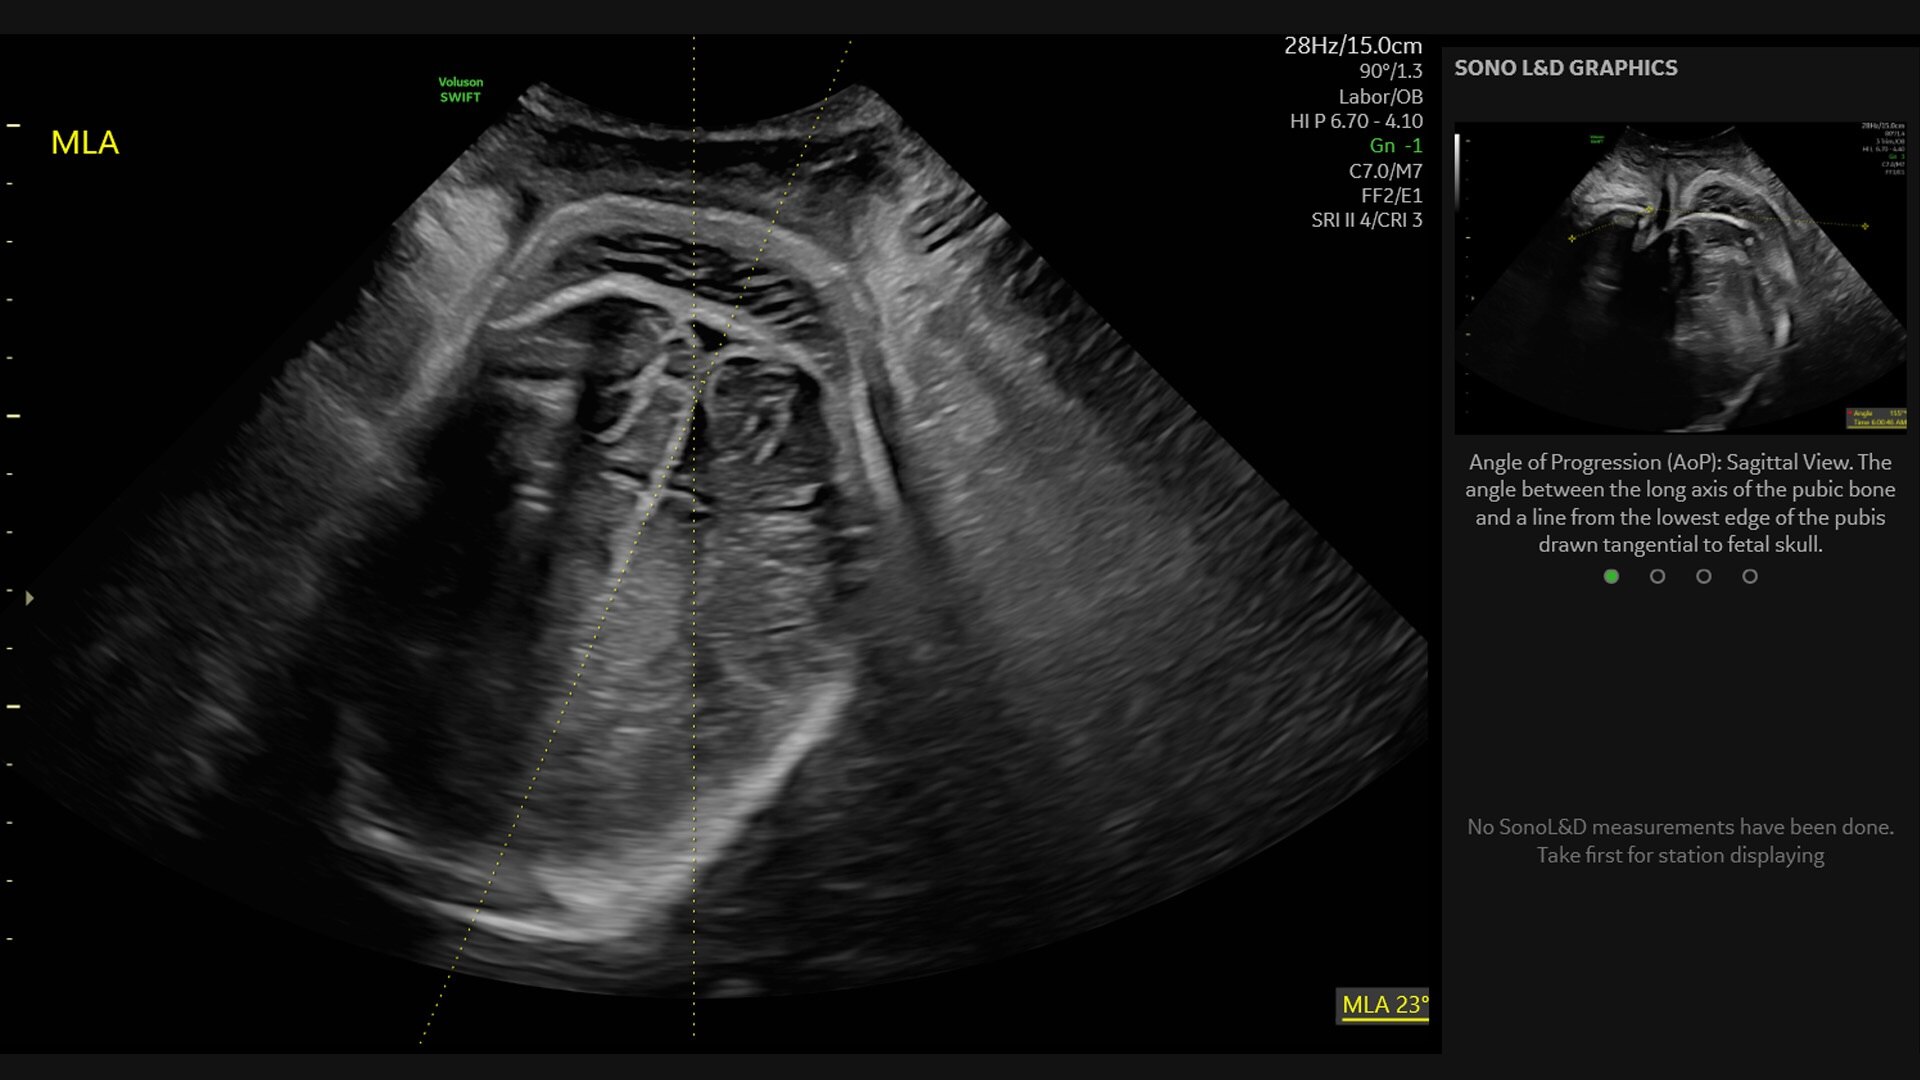

Measures & documents fetal head progression during labor

Measures and documents fetal head progression during labor

Providing objective data for reporting

Enhances patient communication